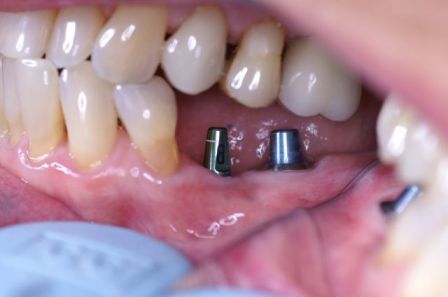

Endosteal implantlar - bu implantlar, cerrahi yöntemle, çene kemiğine direkt olarak implante edilirler. Çevredeki dişeti dokusu iyileştikten sonra, orijinal implanta bağlantı sağlayacak materyali takmak için ikinci bir operasyon gerekir. Son olarak, yapay diş (veya dişler) tek başına veya köprü ya da protez üzerinde grup halinde implanta takılır.

İMPLANTLARIN YERLEŞTİRMESİ VE PROTEZ KADAR SÜRER? Cerrahi işlemin süresi yerleştirilecek implant sayısına ve hastanın koşullarına bağlı olarak yarım saat ile birkaç saat arasında değişebilir. Operasyondan sonra, implant ile kemiğin kaynaşması için (osseointegrasyon) 2-3 ay kadar beklenir. Daha sonra bu implantlar üzerine, birkaç seans süren bir uygulama ile protezler yerleştirilir. İmplantlar dişler çekildikten hemen sonra yerleştirilebilir mi? Evet,günümüzde bu mümkündür.İmplant diş çekimini takiben taze çekim boşluğu içerisine yerleştirilebilir.Buna “immediyat uygulama” denir.